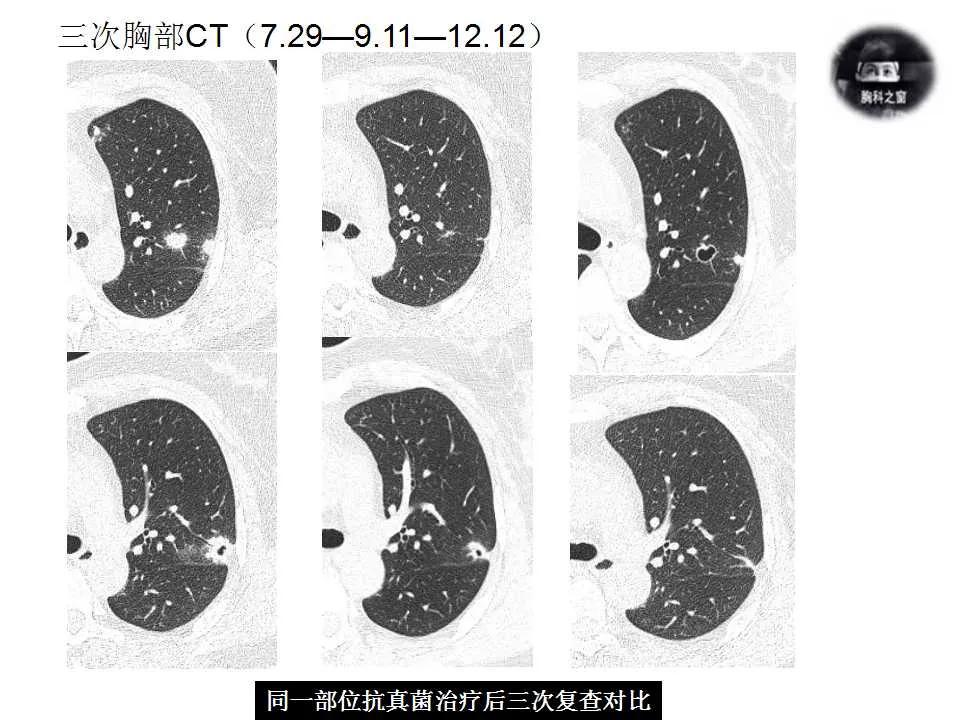

影像诊断:真菌性肺炎,隐球菌可能性大。

追问病史,有近距离接触鸽子史。隐球菌抗原(+)。

肺隐球菌病

治疗及随访